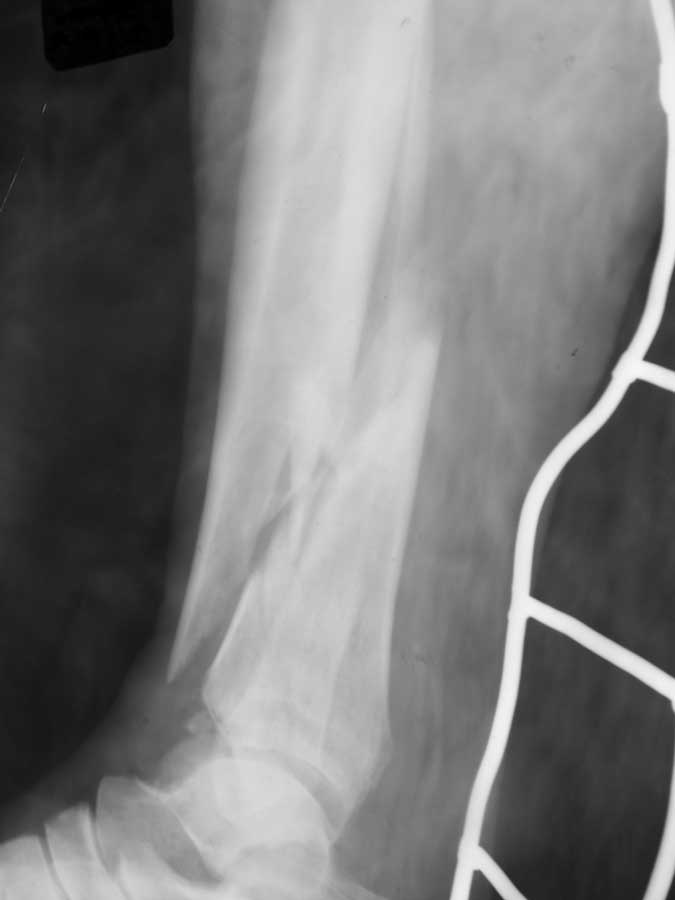

рентгенограмы

Уважаемый Дмитрий, не совсем понятно, когда Вы спрашиваете "что делать". Что делать с переломом или кожными дефектами, или и с тем и другим? Судя по фотографии дефект кожи в нижней трети обусловлен неврозом кортикала б/берцовой кости. Можно было бы попробовать сделать вторичную хирургическую обработку и перфорацию кости спицами дабы дать возможность снизу вырасти грануляциям, а на них уже выполнить аутодермопластику, либо попробовать закрыть дефект местно выкроив кровоснабжаемый лоскут, либо брюшко мышцы. Что касается АВФ, создается впечатление, что он недостаточно стабилен, а отломки немного перерастянуты, хотя по оси смотрится очень прилично. Желаю удачи.

Если судить по рентгенологической картине, то по всей вероятности имеем дело с механизмом непрямой травмы. Такие переломы при хорошем сопоставлении отломков срастаются в пределах 60-70 дней. На фото видны инфицированные раны, будто это участки некроза. Как бы там ни было созерцаемый на фото аппарат "неживой" и нефункциональный, будто его давно не касалась рука врача. Он полностью исчерпал себя, думаю, что он нестабилен. Предлагаю его демонтировать, дать конечности отдохнуть 2-3 недели, за это время провести курс комплексой терапии, как общей, так и местной, затем пациента вновь взять в операционную. Судя по фото, конечность атрофичная, поэтому есть возможность использовать кольца аппарата Илизарова малого диаметра, они фиксируют жестче. На дистальный фрагмент, судя по рентгенограммам, можно установить только одну опору. Чтобы она фиксировала хорошо, необходимо провести спицы (все с напайками с разных сторон) с хорошим перекрестом и разбросом. Для большей стабильности можно временно, на 3 недели, зафиксировать стопу 3/4 кольца и 2 спицами через пятку. На проксимальный фрагмент необходимо установить две опоры, причем нижняя из них должна быть расположена выше ран, чтобы легче было за последними ухаживать. Также провести по две перекрещивающиеся спицы с хорошим перекрестом и натяжением. Осколок можно дополнительно фиксировать спицей с напайкой за пределами ран ИЛИ В КРАЙНЕМ СЛУЧАЕ КОНСОЛЬЮ С НАПАЙКОЙ. Постарайтесь добиться максимально точной репозиции. Только так можно стабилизировать перелом, что позволит пациенту адекватно нагружать конечность, а это и есть путь к решению проблемы.

Кстати, репозиция у Вас неплохая, только большой диастаз между отломками. Если отломки еще податливы, то попробуйте его устранить.

С этим можно определиться только на операционном столе, исходя из податливости при устранении деформации. Судя по выложенным снимкам там сращения нет. Кстати, имеется наружная ротация дистального отломка большеберцовой кости порядка 15 градусов. Об этом свидетельствует то, что он на прямой проекции шире, чем проксимальный.